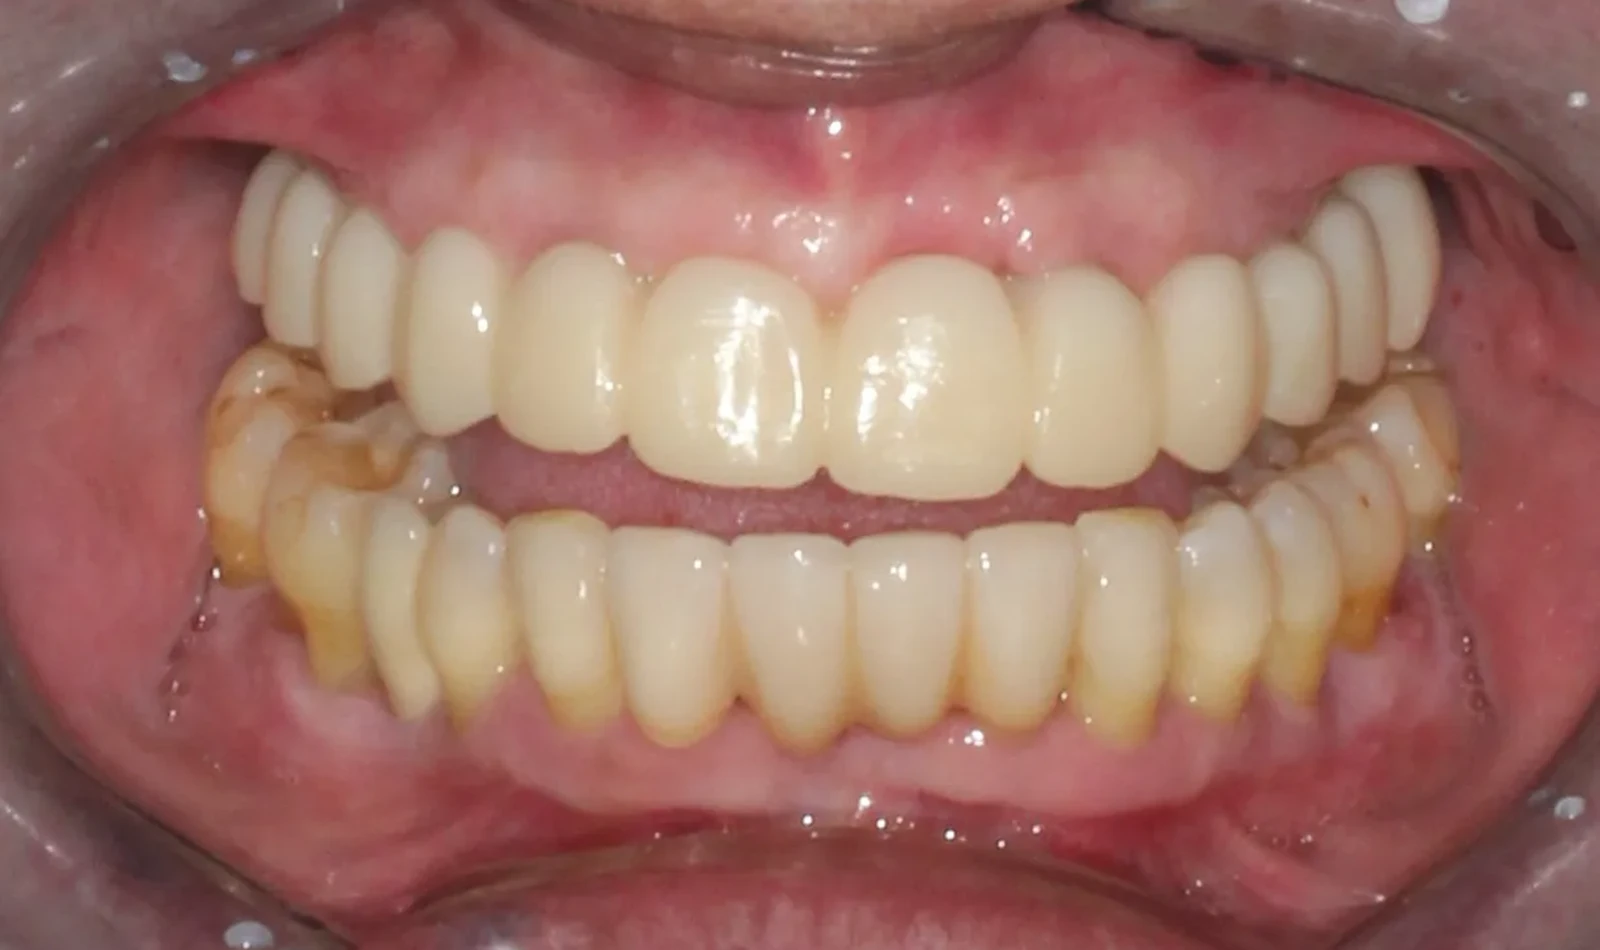

De 61 años nos visita con dientes dañados por caries y una prótesis antigua que ya no podía utilizar. Gracias a la planificación digital y la cirugía guiada, realizamos las extracciones y colocamos implantes con una prótesis fija el mismo día. Recuperó su sonrisa y la confianza de inmediato.